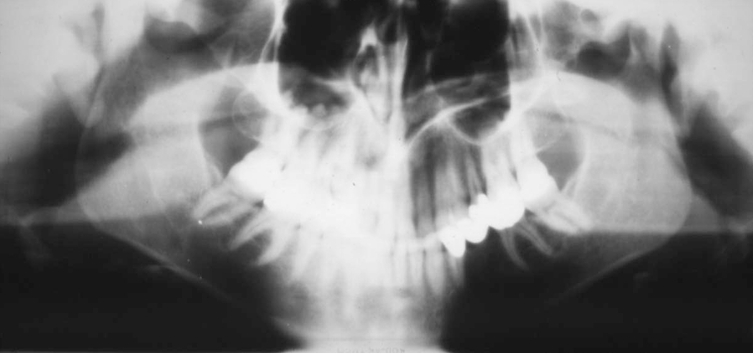

11

What is wrong with this image?

A

too far forward

How well did you know this?